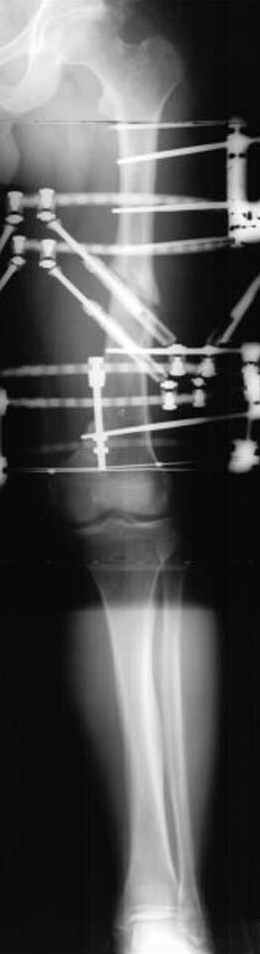

Несколько снимков из моей коллекции, чтобы разьяснить, почему мы до сих пор делаем различные варианты остеотомии.

N3 рисунок окончательный снимок, после операции моя рентгенограмма должен выглядеть примерно как эта картина. На N4 снимке клин перед удалением; N5 послеоперации 3 нед.; N6 окончательная рентгенограмма.

Отправитель: Djoldas Kuldjanov 23 Ноябрь 2004, 18:21

пластическая модель; и коррекция бедра аппаратом Илизарова.

Имею другие снимки тоже, получится как отчет о моей работе.

• Re: Hip joint

Отправитель: Evgueny Tschekashkin 23 Ноябрь 2004, 21:28

Почему не замена гвоздя с рассверливанием, а аппарат?

Отправитель: Evgueny Tschekashkin 24 Ноябрь 2004, 21:09

хотя даже если бы и инфекция , то nail exchange с рассверливанием канала - вариант дебрайдмента) Я думаю, что последовательность развития событий:

Узкий к-м канал - тонкий гвоздь- усталостный перелом дистальных винтов - развитие нестабильности и как ее результат остеолиз вокруг гвоздя - деформация анатомической оси бедра. Похоже, что я понял почему аппарат, а не новый гвоздь:-)